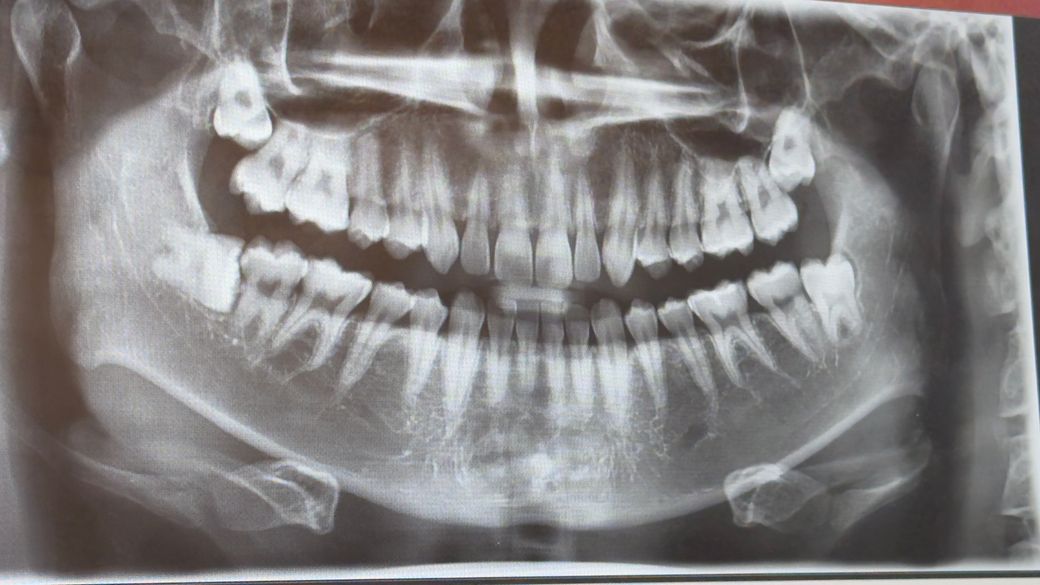

통증같은건 따로 없었는데 냄새가 좀 나는거같길래 오른쪽 아래에 똑바로 나있는건 동네 병원에서 뽑기로 했습니다. 위에 두개나 왼쪽에 누워있는거의 경우 난이도가 많이 높은지 걱정입니다. 이 전에 갔던 병원에선 대학병원에 가라 했었는데 난이도가 많이 어려운건가요?55글자 더 채워주세요.

아래 누워있는 수평매복 사랑니는 난이도가 높은 편입니다. 윗쪽 양쪽 2개 사랑니고 난이도가 높은 편입니다. 대학병원 아니라도 구강외과 전문의가 진료하는 동네 치과 가도 됩니다.

일반 치과에서 발치를 하는 것도 불가능해보이지는 않습니다만 혹시 모르니 대학병원 가시는 게 낫습니다.

저 엑스레이 만으로 왼쪽 위(사진상) 사랑니의 난이도를 판별하기는 쉽지 않습니다.

CT등을 찍어봐야 될거 같습니다.

왼쪽아래(사진상) 사랑니는 난이도가 낮습니다.

사랑니 난이도가 꽤 높을것같습니다 매복 깊이도 깊고 신경과의 거리고 많이 가까운것같습니다.

오른쪽 아래와 왼쪽 아래에 있는 사랑니의 경우에는 매복되어 있기 때문에 발치 발치도가 높은 편에 속합니다. 구강 외과 전문의 선생님한테 발치를 한다면 조금 더 편하게 발치를 할 수 있을 것으로 생각됩니다.